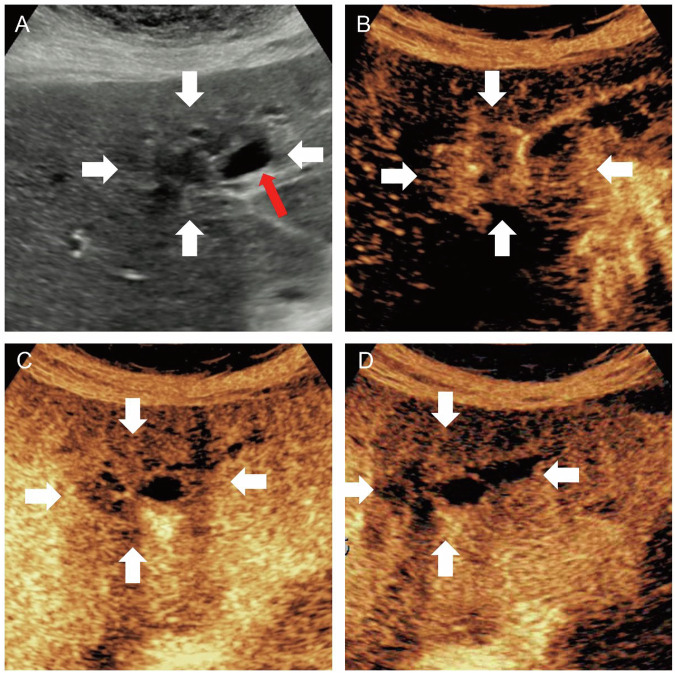

目的:磁共振成像(MRI)可将块状肝内胆管癌(MF-ICCs)分为导管型和实质型。我们的目的是根据超声(US)结果将MF-ICC分为胆道型和实质型,并探讨它们在超声造影(CEUS)模式、临床病理特征和预后方面的差异。方法:在本研究中,回顾性纳入了来自两家医院的141例经病理证实的MF-ICC患者。根据超声图像胆管扩张的征象,将胆道内胆囊炎(MF-ICC)分为胆道内胆囊炎(bmf - icc)和实质内胆囊炎(pmf - icc)。从医疗记录中收集临床病理、影像学和短期生存数据并进行比较。结果:141例患者(61.96±10.15岁,男性83例)中,bMF-ICCs(33/141, 23.4%)的CEA≥5µg/L(42.4%比20.2%,p = 0.01)、微血管侵犯(54.5%比10.2%,p = 0.01)显著增加。结论:基于US将MF-ICCs亚分类为胆道型和实质型有助于区分临床病理特征。关键相关性声明:超声将形成团块的肝内胆管癌(MF-ICC)分为胆道(bMF-ICC)和实质(pMF-ICC)亚型,可以在手术前提供临床病理和预后信息。重点:我们利用超声将形成团块的肝内胆管癌分为胆道型和实质型。胆道型和实质型具有不同的临床病理特征和术后结果。50 mm以上及以下胆道型表现出不同的不良临床病理特征。我们的分类在临床病理特征上与MRI分类有一定的相似之处。

Objective: Mass-forming intrahepatic cholangiocarcinomas (MF-ICCs) can be classified into ductal and parenchymal types using magnetic resonance imaging (MRI). We aimed to subclassify MF-ICC into biliary and parenchymal types based on ultrasound (US) findings and to investigate the differences in their contrast-enhanced ultrasound (CEUS) patterns, clinicopathologic features, and prognosis.

Methods: In this study, 141 patients who underwent US with pathologically proven MF-ICC from two hospitals were retrospectively enrolled. MF-ICCs were divided into biliary (bMF-ICCs) and parenchymal MF-ICC (pMF-ICCs) based on the signs of bile duct dilation in US images. Clinicopathological, imaging, and short-term survival data were collected from medical records and compared.